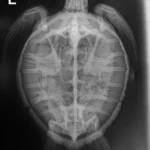

8.6 lb non-FP juvenile green

Moderate plastron abrasions and bruising, wounds on all 4 flippers, abrasions on edge of both left and right marginal scutes, moderate abrasions to carapace.